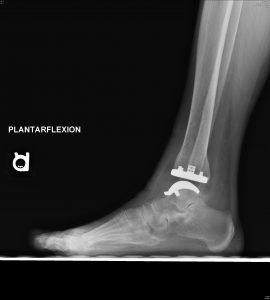

Follow-up is too short at this point to report outcomes for the Vantage. However, my colleagues and I have been collecting data on every Vantage that we implant, including validated patient-reported outcomes, accepted objective outcomes measures and standardized radiographic evaluations. (Fig 10 A and B) To date, our observations reflect high patient satisfaction, low complication rates and a trend toward favorable range of motion confirmed with objective postoperative radiographic dorsiflexion and plantarflexion measurements. While my colleagues and I initially limited the Vantage to end-stage ankle arthritis with minimal deformity, more recently we expanded indications to include varus and valgus ankle arthritis. At early follow-up our results are equally favorable for end-stage ankle arthritis with and without deformity.